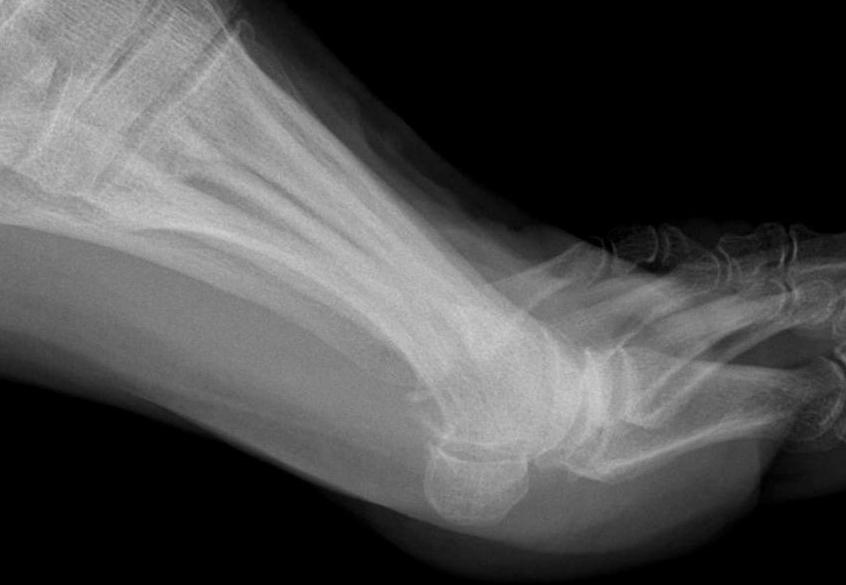

X-ray

Osteoarthritis

- joint space narrowing

- dorsomedial osteophyte

Mild to moderate OA

Severe OA